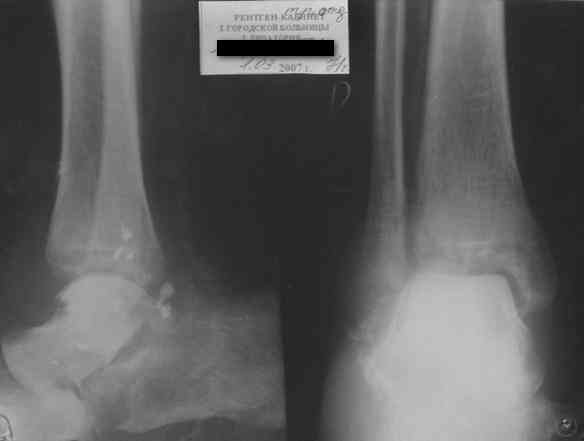

Re: Редкое повреждение - полный вывих тарана!

Последний снимок